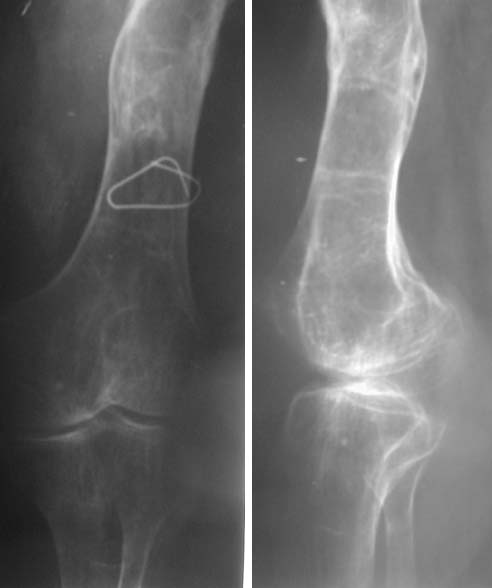

Судя по представленному снимку, есть 3 деформации – Варусная в области ложного сустава - 70°, Вальгусная - 35° в средней трети бедра, и ещё одна вальгусная 8° в области дистального метаэпифиза бедренной кости. Если бы пациент попал ко мне, я сделал бы трилокальный остеосинтез – Открытый погружной копрессионный в области ложного сустава, остеотоми на вершине деформации средней трети бедра для удлинения и коррекции деформации и коррегирующую остеотомию через верхний край мыщелков бедренной кости. Для оппонентов такой тактики сразу оговорюсь, что коррекция анатомической и механической оси при наличии срастающегося ложного сустава критична для профилактики рефрактуры.